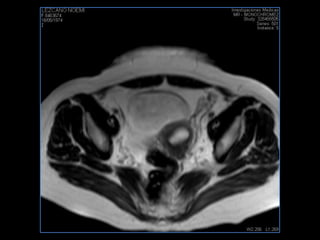

PROTOCOLO pelvis SAG T2, Y FAT SAT (FINOS) AXIAL T1  AX FAT SAT CON   GADOLINIO :  AX T1 Y COR T1 SAT: NO  FASE: RL THK: 3MM  COIL:  GAP: (FACTOR 1.4) 1MM FOV: 40 CM NEX:2 SINCRONIZACION RESPIRATORIA EN 3 O 4 CICLOS ALE